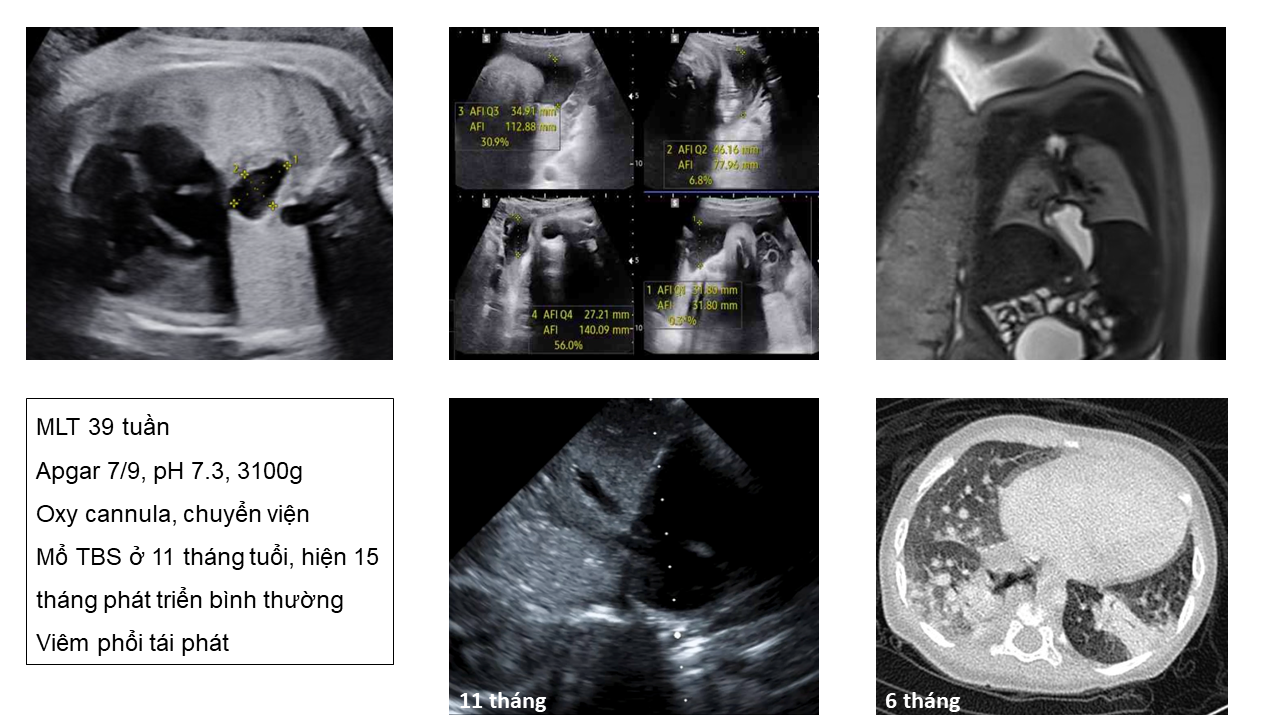

Thoát vị hoành - phải hay trái?